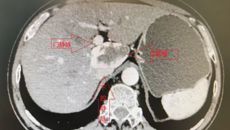

近日,54岁的刘先生,因腹痛到医院检查时发现肝尾状叶6x5cm巨大血管瘤。一听说是肿瘤,刘先生慌了神,在亲戚的建议下,来到广西国际壮医医院找到肝胆外科副主任医师韦邦宁求助。 “亲戚推荐我来找韦医生看看,我也上网了解了韦医生的信息,知道他做肝脏手术的经验丰富,我愿意相信他。”刘先生表示。 韦邦宁将患者收治入院,完善相关检查,经过仔细阅片后,他知道这台手术的困难程度不小。 患者术前CT “大的肝脏血管瘤是定时炸...07.082022